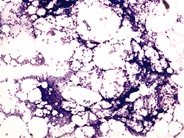

A 73-year-old man without prior personal or family history of anemia developed a chronic hemolytic anemia characterized by an absolute reticulocyte count of 347 000/mm 3 (13%) and spherocytic red-cell morphology (see panel A). Antiglobulin testing was negative but osmotic fragility testing was positive. Bone marrow biopsy was hypercellular with a decreased M:E ratio and dysplastic erythroid precursors. Standard cytogenetics reported an interstitial deletion of 5q13-33 and a gain of material on 14q22. High-density single-nucleotide polymorphism array–based karyotyping revealed 6 deletion regions on chromosome 5 and 3 deletion regions on chromosome 14, including loss of 14q23.1-24.2. Taken together with the cytogenetic studies, a complex rearrangement of chromosomes 5 and 14 resulted in the net losses. One of the 14q-deletion regions contains SPTB, rendering this patient haploinsufficient for the gene encoding the β-spectrin protein. Thus, this patient’s complex rearrangement resulted in a phenocopy of hereditary spherocytosis type 2 (OMIM ) (see panel B). This patient’s case demonstrates the clinical utility of high-density array karyotyping to define atypical clinical presentations and highlights the variable natural history of myelodysplastic syndromes.(Panel A) Blood smear from a 73-year-old man with a myelodysplastic syndrome and acquired spherocytosis. (Panel B) Blood smear from a 65-year-old man with autosomal-dominant hereditary spherocytosis. Red arrows indicate microspherocytes and blue arrows indicate polychromatophilic cells (reticulocytes).